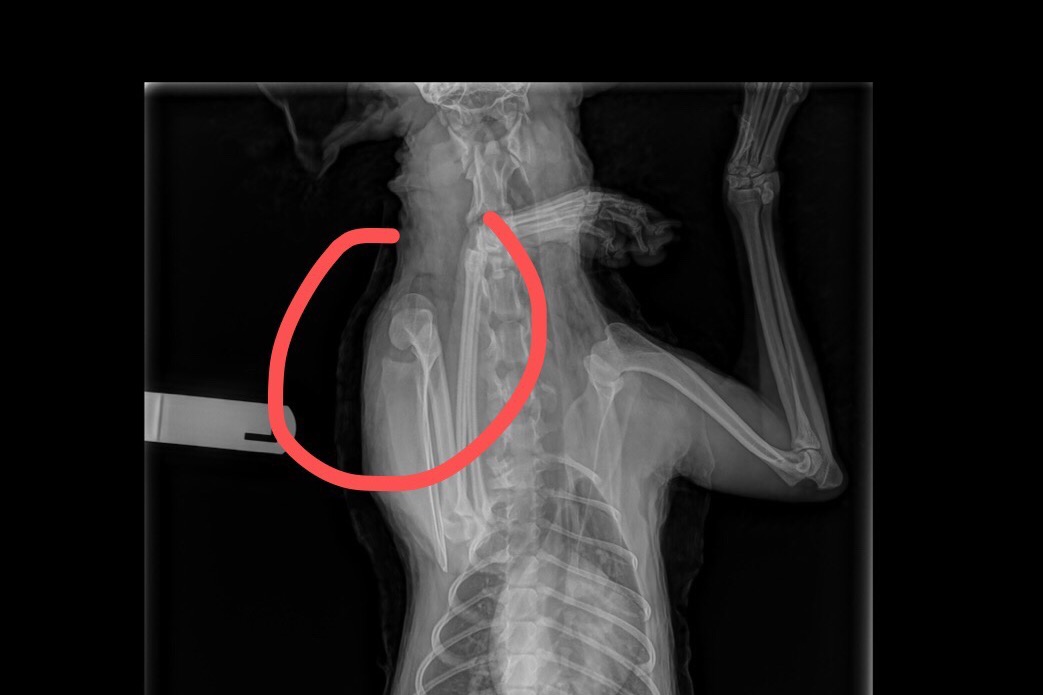

I took him to the vet. He was diagnosed with a shoulder luxation, which is rare for dogs without any trauma, but the instability of the shoulder is usually common/generic for his breed. I spent nearly 2K on the bandaging and was hoping he can go back to normal after two weeks. But he’s gotten worse, his energy level is lower and he still can’t use his left arm. Poor guy struggles with 3 legs, when he pees, he tumbles :(

(This is Basil trying to walk with 3 leg )